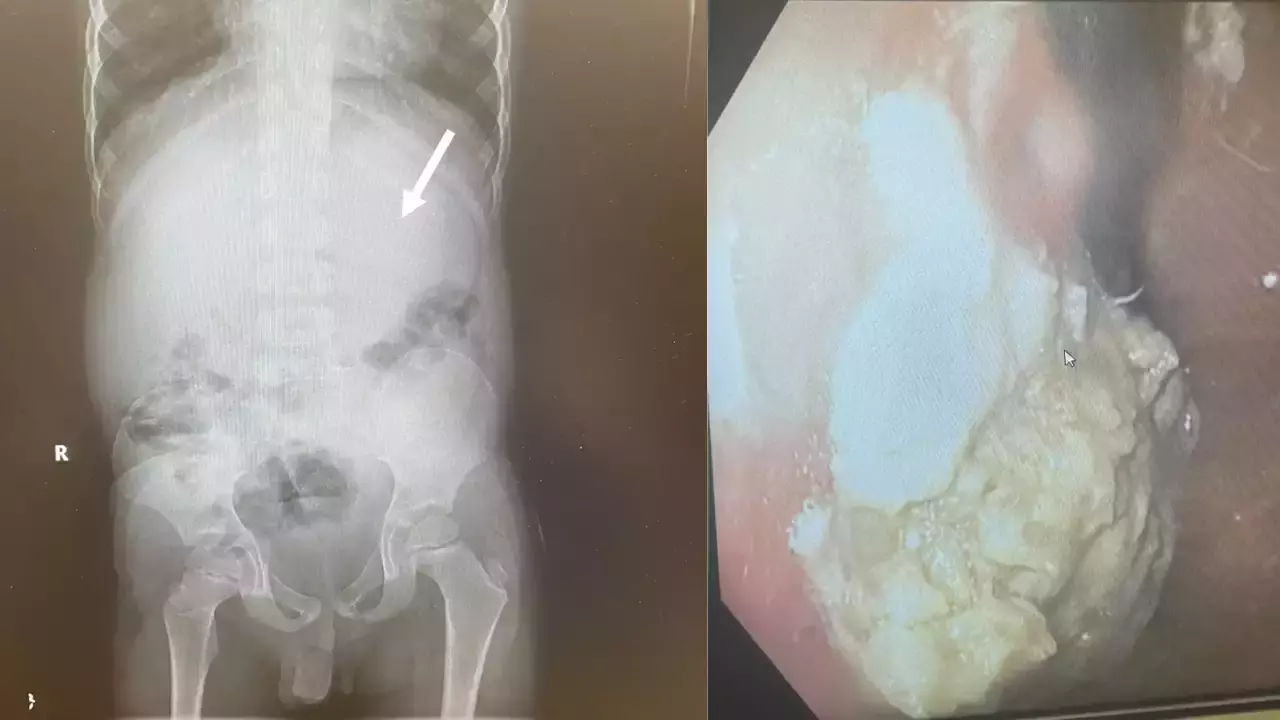

എന്ഡോസ്കോപിക് ചിത്രങ്ങള്

വാഷിംഗ്ടണ്: അമേരിക്കയിലെ ഒഹിയോയില് 40 ച്യൂയിംഗ് ഗം വിഴുങ്ങിയ അഞ്ചു വയസുകാരന് അടിയന്തര ശസ്ത്രക്രിയ നടത്തി.കുട്ടിയുടെ ആമാശംയ ബ്ലോക്കായതിനെ തുടര്ന്നാണ് ശസ്ത്രക്രിയ നടത്തേണ്ടി വന്നതെന്ന് ഡോക്ടര്മാര് പറഞ്ഞു. ച്യൂയിംഗ് ഗം കഴിച്ചതു മൂലം ദഹനവ്യവസ്ഥ തടസപ്പെട്ടിരുന്നു. വയറുവേദനയും വയറിളക്കവും ഉണ്ടായതിനെ തുടര്ന്നാണ് കുട്ടിയെ ആശുപത്രിയിലെത്തിച്ചത്.

ക്ലീവ്ലാൻഡ് ക്ലിനിക്കിലെ ഡോ. ചിസൈറ്റ് ഇഹിയോനുനെക്വുവിന്റെ നേതൃത്വത്തിലുള്ള സംഘമാണ് ശസ്ത്രക്രിയ നടത്തിയത്. ഫോഴ്സ്പ്സ് ഉപയോഗിച്ചാണ് ഡോക്ടർമാർ ഗം നീക്കം ചെയ്തത്.ച്യൂയിംഗ് ഗം ശരീരത്തിൽ ഏഴ് വർഷത്തോളം നിലനിൽക്കുമെന്ന മുന്നറിയിപ്പിനെ വിദഗ്ധര് തള്ളിക്കളഞ്ഞു. “നിങ്ങൾ ഒരു കഷണം ഗം വിഴുങ്ങിയാൽ, അത് ഏകദേശം 40 മണിക്കൂർ കഴിഞ്ഞ് നിങ്ങളുടെ വിസര്ജ്യത്തിലൂടെ പുറത്തുവരും,” ഡയറ്റീഷ്യൻ ബെത്ത് സെർവോണി ക്ലീവ്ലാൻഡ് പറഞ്ഞു. എന്നാൽ പുതിന ഫ്രഷ് ച്യൂയിംഗ് ഗം കഴിക്കുന്നത് ശീലമാക്കരുതെന്നും ദഹിപ്പിക്കാൻ കഴിയാത്തതിനാൽ ഇത് കുടൽ അസ്വസ്ഥത ഉണ്ടാക്കുമെന്നും അദ്ദേഹം പറഞ്ഞു. “നിങ്ങൾ ഇത് എല്ലാ ദിവസവും അല്ലെങ്കിൽ ഒന്നിലധികം തവണ ചെയ്താൽ, ഇത് കുടൽ തടസ്സത്തിന് കാരണമാകും,” സെർവോണി മുന്നറിയിപ്പ് നൽകി.